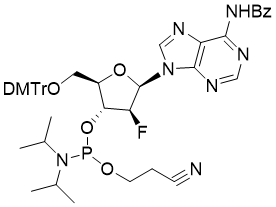

馬鞍山致研生物醫(yī)藥科技有限公司成立于馬鞍山市鄭浦港新區(qū)現(xiàn)代產(chǎn)業(yè)園。公司專(zhuān)注于生物小分子、醫(yī)藥中間體相關(guān)產(chǎn)品的研發(fā)和生產(chǎn),產(chǎn)品主要包括DNA亞磷酰胺單體、RNA亞磷酰胺單體、特殊單體以及按照客戶(hù)要求定制的RNA和DNA,并且公司提供定制合成等方面的研究服...

馬鞍山致研生物醫(yī)藥科技有限公司成立于馬鞍山市鄭浦港新區(qū)現(xiàn)代產(chǎn)業(yè)園。公司專(zhuān)注于生物小分子、醫(yī)藥中間體相關(guān)產(chǎn)品的研發(fā)和生產(chǎn),產(chǎn)品主要包括DNA亞磷酰胺單體、RNA亞磷酰胺單體、特殊單體以及按照客戶(hù)要求定制的RNA和DNA,并且公司提供定制合成等方面的研究服...